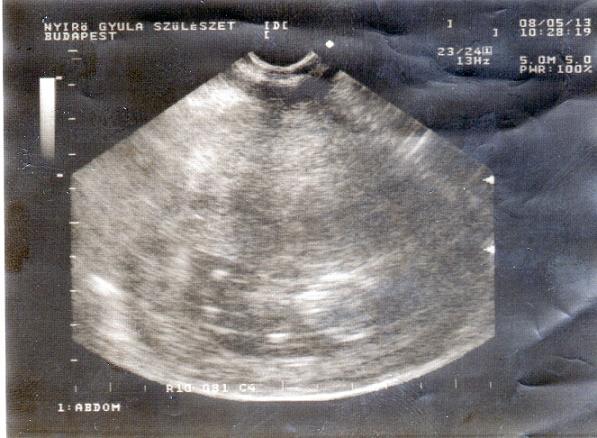

A 72 óra bentlét alatt megcsinálnak minden vizsgálatot a babán...hallás, látás, vért vesznek, uh......stb.

33. hét